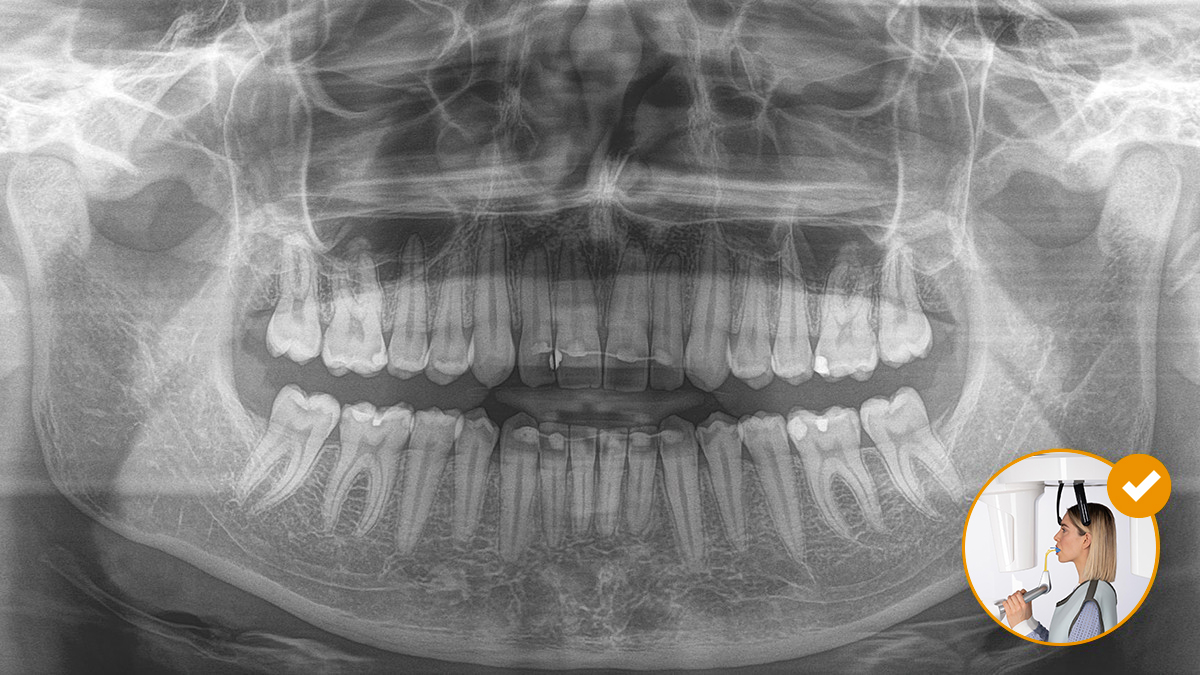

El posicionamiento correcto del paciente permite obtener imágenes de alta calidad que respaldan un diagnóstico preciso y facilitan y mejoran la experiencia del paciente.

El resultado: Escaneos precisos gracias al bloque de mordida oclusal